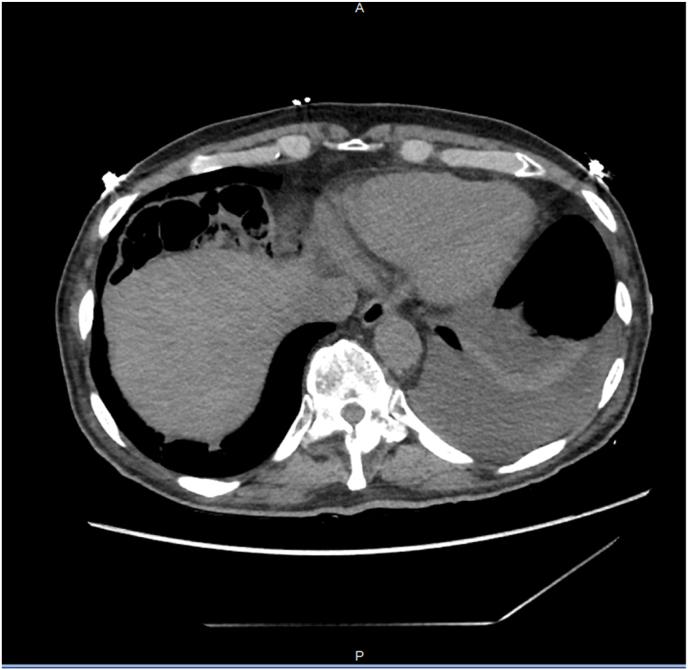

奇莱迪蒂综合征:一名心力衰竭患者的结构移位。

Chilaiditi syndrome: A structural displacement in a heart failure patient.

CASE PRESENTATION

In this interesting case, we discover lingering dyspnea in our 79 year old male with a past medical history of asthma and heart failure with preserved ejection fraction admitted for acute heart failure exacerbation with reduced ejection fraction along with a new incidental finding of Chilaiditi's sign on chest radiograph. Patient received optimal diuretics and guideline-directed medical treatment for heart failure exacerbation, but mild dyspnea with pleuritic chest pain persisted. Dyspnea with pleurisy was likely attributed to a structural anatomical defect (Chilaiditi's sign) that can be picked up on imaging.

CONCLUSION

Chilaiditi syndrome can be an incidental cause of ongoing persistent dyspnea, and if symptoms are severe, intervention can be warranted for symptomatic resolution.

在这个有趣的病例中,我们发现一名79岁男性患者持续存在呼吸困难,该患者既往有哮喘病史和射血分数保留的心力衰竭病史,此次因射血分数降低的急性心力衰竭加重入院,胸部X线片上偶然发现Chilaiditi征。患者接受了最佳利尿剂治疗及针对心力衰竭加重的指南指导药物治疗,但仍持续存在轻度呼吸困难并伴有胸膜炎性胸痛。胸膜炎性呼吸困难可能归因于影像学上可发现的结构性解剖缺陷(Chilaiditi征)。

结论

Chilaiditi综合征可能是持续性呼吸困难的偶然原因,如果症状严重,可考虑进行干预以缓解症状。